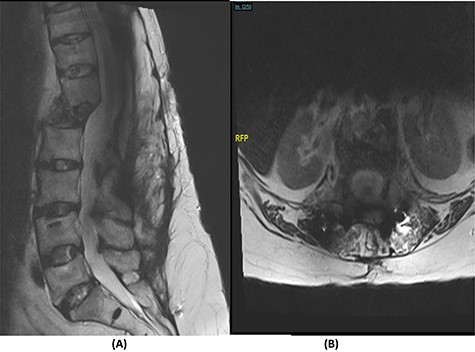

Fourteen months later, the patient presented to the ED complaining of generalized body pain associated with malaise. The neurological examination was unremarkable. An MRI of the lumbar spine showed recurrence of the lesion with loosening and pullout of the implant, kyphosis and dislocation, with cord compression and collection (Fig. 2). Computed tomography (CT) scan showed a burst fracture of the L1 vertebra with loose screws (Fig. 3). CRP was 21 mg/l, ESR was 115 mm/h and procalcitonin was 0.051 ng/ml. The decision was made to do a CT-guided biopsy from the left paraspinal mass of T12–L1. The tissue biopsy was subjected to TB-polymerase chain reaction testing and acid-fast bacillus culture; both results were positive for M. tuberculosis. The patient was diagnosed with TB spondylitis and was started on the full anti-TB four-drug regimen.

(A) T2-weighted sagittal spine MRI demonstrating changes at the thoracolumbar spine with previous decompression for pathological fracture of L1 vertebra. There is interval progression of the disease with a soft tissue mass at the previous site extending to the prevertebral and epidural spaces, compressing the neural element. (B) T2-weighted axial spine MRI of the corresponding level of L1 vertebral body.